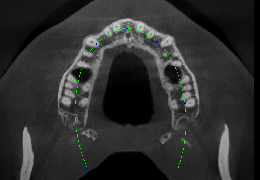

View X-Ray CT & MRI Scans Fast and Easily

Designed for surgeons, Pro Surgical 3D makes it easy to view patient scans quickly. Pro Surgical 3D facilitates the optimal 3D treatment and assessment workflows based on X-ray CT and MRI scans – and best of all, it’s FREE!

High-quality and fast 3D reconstruction and 3D rendering

Performs 3D reconstruction and volume rendering.

Axis-aligned cropping with context.

Side-by-side comparative assessment for pre- and post-operative scans.